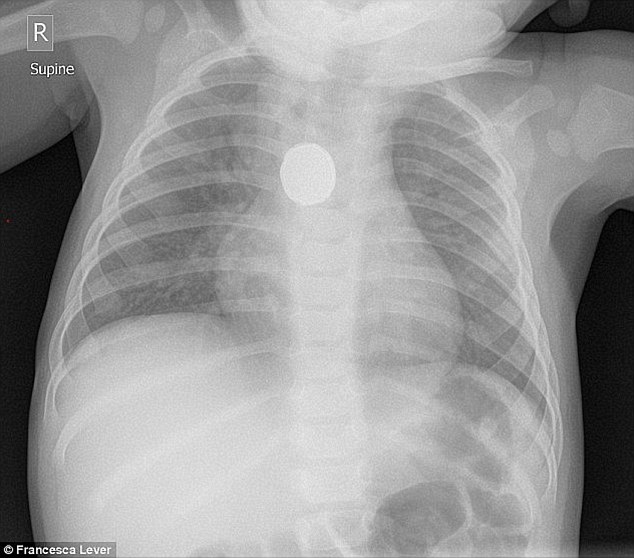

Părinții Isabellei Rees, fetița care a murit după ce a înghițit o baterie, lansează acuzații grave: ”Medicii au refuzat radiografia!”